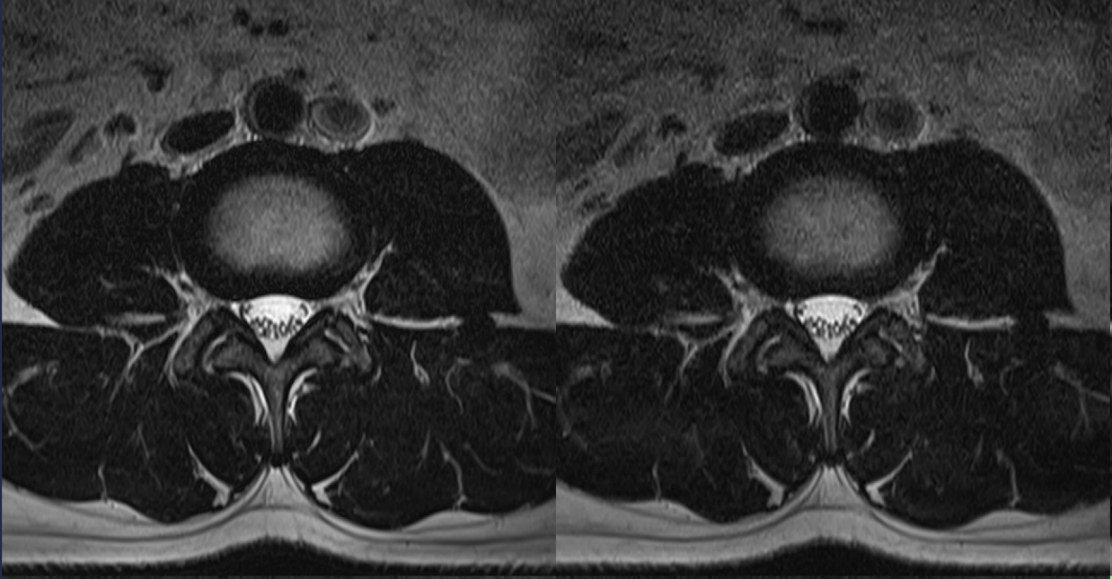

Original

Compressed SPEEDER 2.0

Compressed SPEEDER 2.5

Время сканирования 3:10

Vantage Orian 1.5T

Время сканирования 1:46

Vantage Orian 1.5T

Время сканирования 1:18

Vantage Orian 1.5T